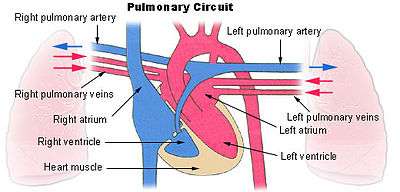

The pulmonary veins are large blood vessels that receive oxygenated blood from the lungs and drain into the left atrium of the heart. There are four pulmonary veins, two from each lung. The pulmonary veins are among the few veins that carry oxygenated blood.

The right pulmonary veins (contains oxygenated blood) pass behind the right atrium and superior vena cava; the left in front of the descending thoracic aorta.

The pulmonary veins play an essential role in respiration, by receiving blood that has been oxygenated in the alveoli and returning it to the left atrium.

As part of the pulmonary circulation they carry oxygenated blood back to the heart, as opposed to the veins of the systemic circulation which carry deoxygenated blood.

Bronchi, bronchial tree, and lungs Pulmonary circuit

Pulmonary circuit Heart seen from above.